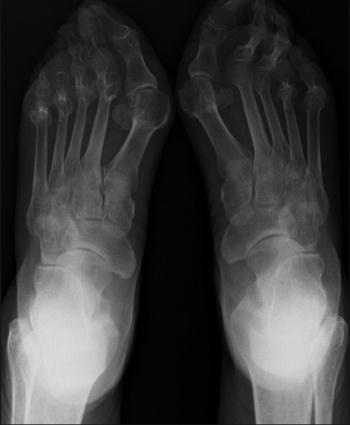

Joint deformities of the feet secondary to inflammatory joint disease

Joint deformities of the feet secondary to inflammatory joint disease(click to enlarge)